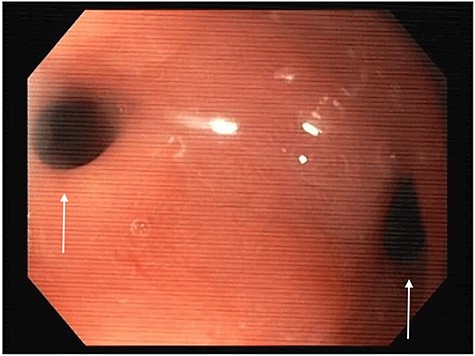

The computed tomography (CT) scan with oral contrast revealed a GGF (see Fig. 1). The upper gastrointestinal endoscopy confirmed a GGF and also demonstrated a stenosis of the gastro-jejunal anastomosis (GJA) (see Fig. 2).

Esophagogastroduodenoscopy image showing a gastro-gastric fistula (on the right) and stenosis of the gastro-jejunal anastomosis (on the left), marked with arrows.